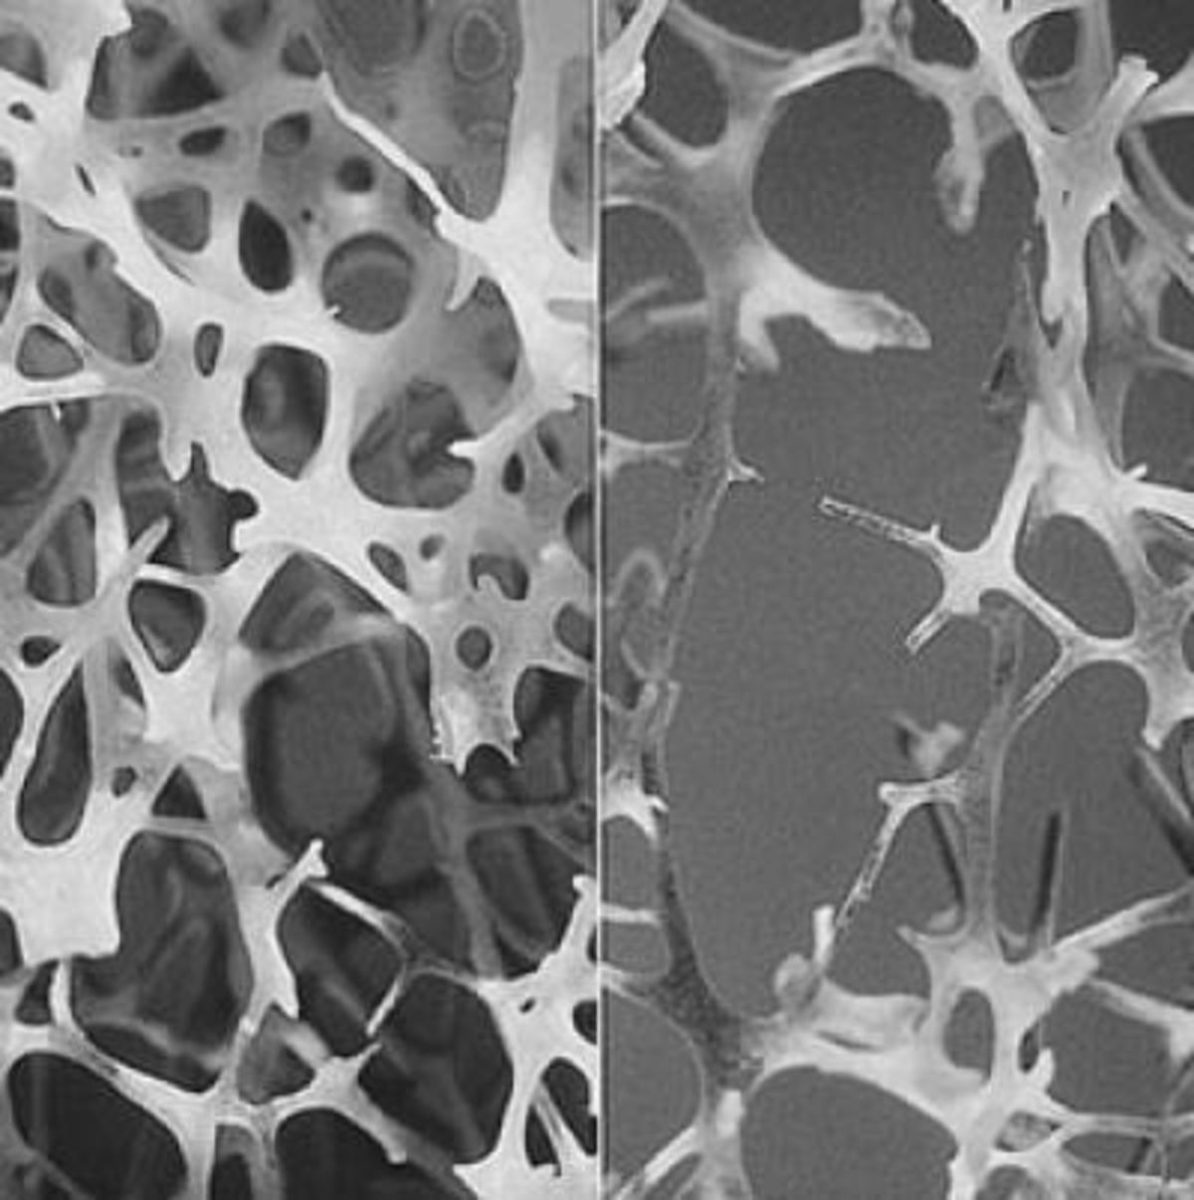

Ιδιαίτερα ακριβή αποδεικνύεται για το σύστημα υγείας η διαχείριση της οστεοπόρωσης και κυρίως των καταγμάτων που οφείλονται σε αυτή, εφόσον δεν διαγνωστεί και αντιμετωπιστεί εγκαίρως, σύμφωνα με μελέτη της Εθνικής Σχολής Δημόσιας Υγείας (ΕΣΔΥ). Συγκεκριμένα, το συνολικό άμεσο κόστος της οστεοπόρωσης, συμπεριλαμβανομένων και διαδικασιών αποκατάστασης, για το ΕΣΥ μπορεί να αγγίξει και τα 890 εκατομμύρια ευρώ.

Μάλιστα, η εμφάνιση ενός κατάγματος αυξάνει κατά 300% το μέσο, ανά ασθενή, ετήσιο κόστος, κυρίως στην περίπτωση κατάγματος ισχίου, όπου απαιτείται χειρουργική επέμβαση.

Το μέσο ετήσιο κόστος της νόσου, όταν η μετεμμηνοπαυσιακή ασθενής έχει υποστεί κάταγμα στο παρελθόν, ξεπερνά τα 2000 ευρώ, ποσοστό 78% υψηλότερο από τις περιπτώσεις που δεν προϋπάρχει κάταγμα. Τη μεγαλύτερη επιβάρυνση στο σύστημα υγείας προκαλούν τα κατάγματαισχίου, με μέσο ετήσιο κόστος πάνω από 4.300 ευρώ.

Η συχνότητα της νόσου αγγίζει το 30%, όταν μόνο στις μετεμμηνοπαυσιακές γυναίκες, άνω των 50 ετών, το 79% παρουσιάζει κάποιο παράγοντα κινδύνου, όπως χαμηλό δείκτη μάζας σώματος (BMI), προηγούμενο κάταγμα, κάπνισμα ή οικογενειακό ιστορικό. Η Οστεοπόρωση είναι το τρίτο ακριβότερο νόσημα μετά το Διαβήτη και την Υπέρταση, σε ότι αφορά στο κόστος διαχείρισης από το ΕΣΥ.